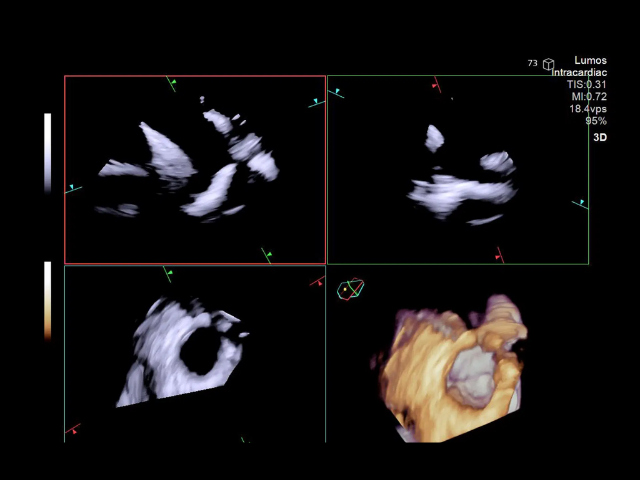

AcuNav Lumos

In 2024, Siemens Healthineers launched the AcuNav Lumos 4D ICE catheter with improved biplane imaging and multiplanar reconstruction (MPR), better leak detection with real-time 4D color Doppler, and compatibility to ACUSON Origin, an advanced cardiac ultrasound system with integrated AI features for supporting enhanced clinical decision making.Â